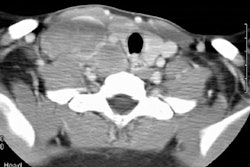

Intrathoracic lymphoproliferative disorders (LPDs) span a spectrum of benign lesions to those that are frankly malignant or have a malignant potential. The clonality of lymphoid populations is helpful in separating benign from malignant disorders. Polyclonality is usually reflective of benign disease, while monoclonality is usually indicative of malignancy. Stimulation of bronchus-associated lymphoid tissue (or BALT) and the Ebstein-Barr virus (EBV) are thought to play key roles in these disease processes. It has been postulated that the EBV genome may act as a stimulant, either as a primary or reactivated agent, particularly in disorders such as infectious mononucleosis and the post-transplant lymphoproliferative disorder.

Several generalizations have been made regarding the LPDs. These are: 1- older symptomatic patients have a more aggressive disease (i.e., lymphoma); 2- benign LPDs tend to be focal (i.e., lung or lymph nodes) and pleural effusions are rare in benign disease; and 3- the post-transplant LPDs may have a variety of radiographic findings (i.e., infiltrates, masses, and/or adenopathy). The site of disease may also provide a clue to the diagnosis. Parenchymal lung abnormalities are found in association with plasma cell granuloma (pulmonary pseudotumor), pseudolyphoma, and lymphatoid granulomatosis (angiocentric immunoproliferative lesion). While mediastinal disease suggests Castleman's disease, infectious mononucleosis, or angioimmunoblastic lymphadenopathy.